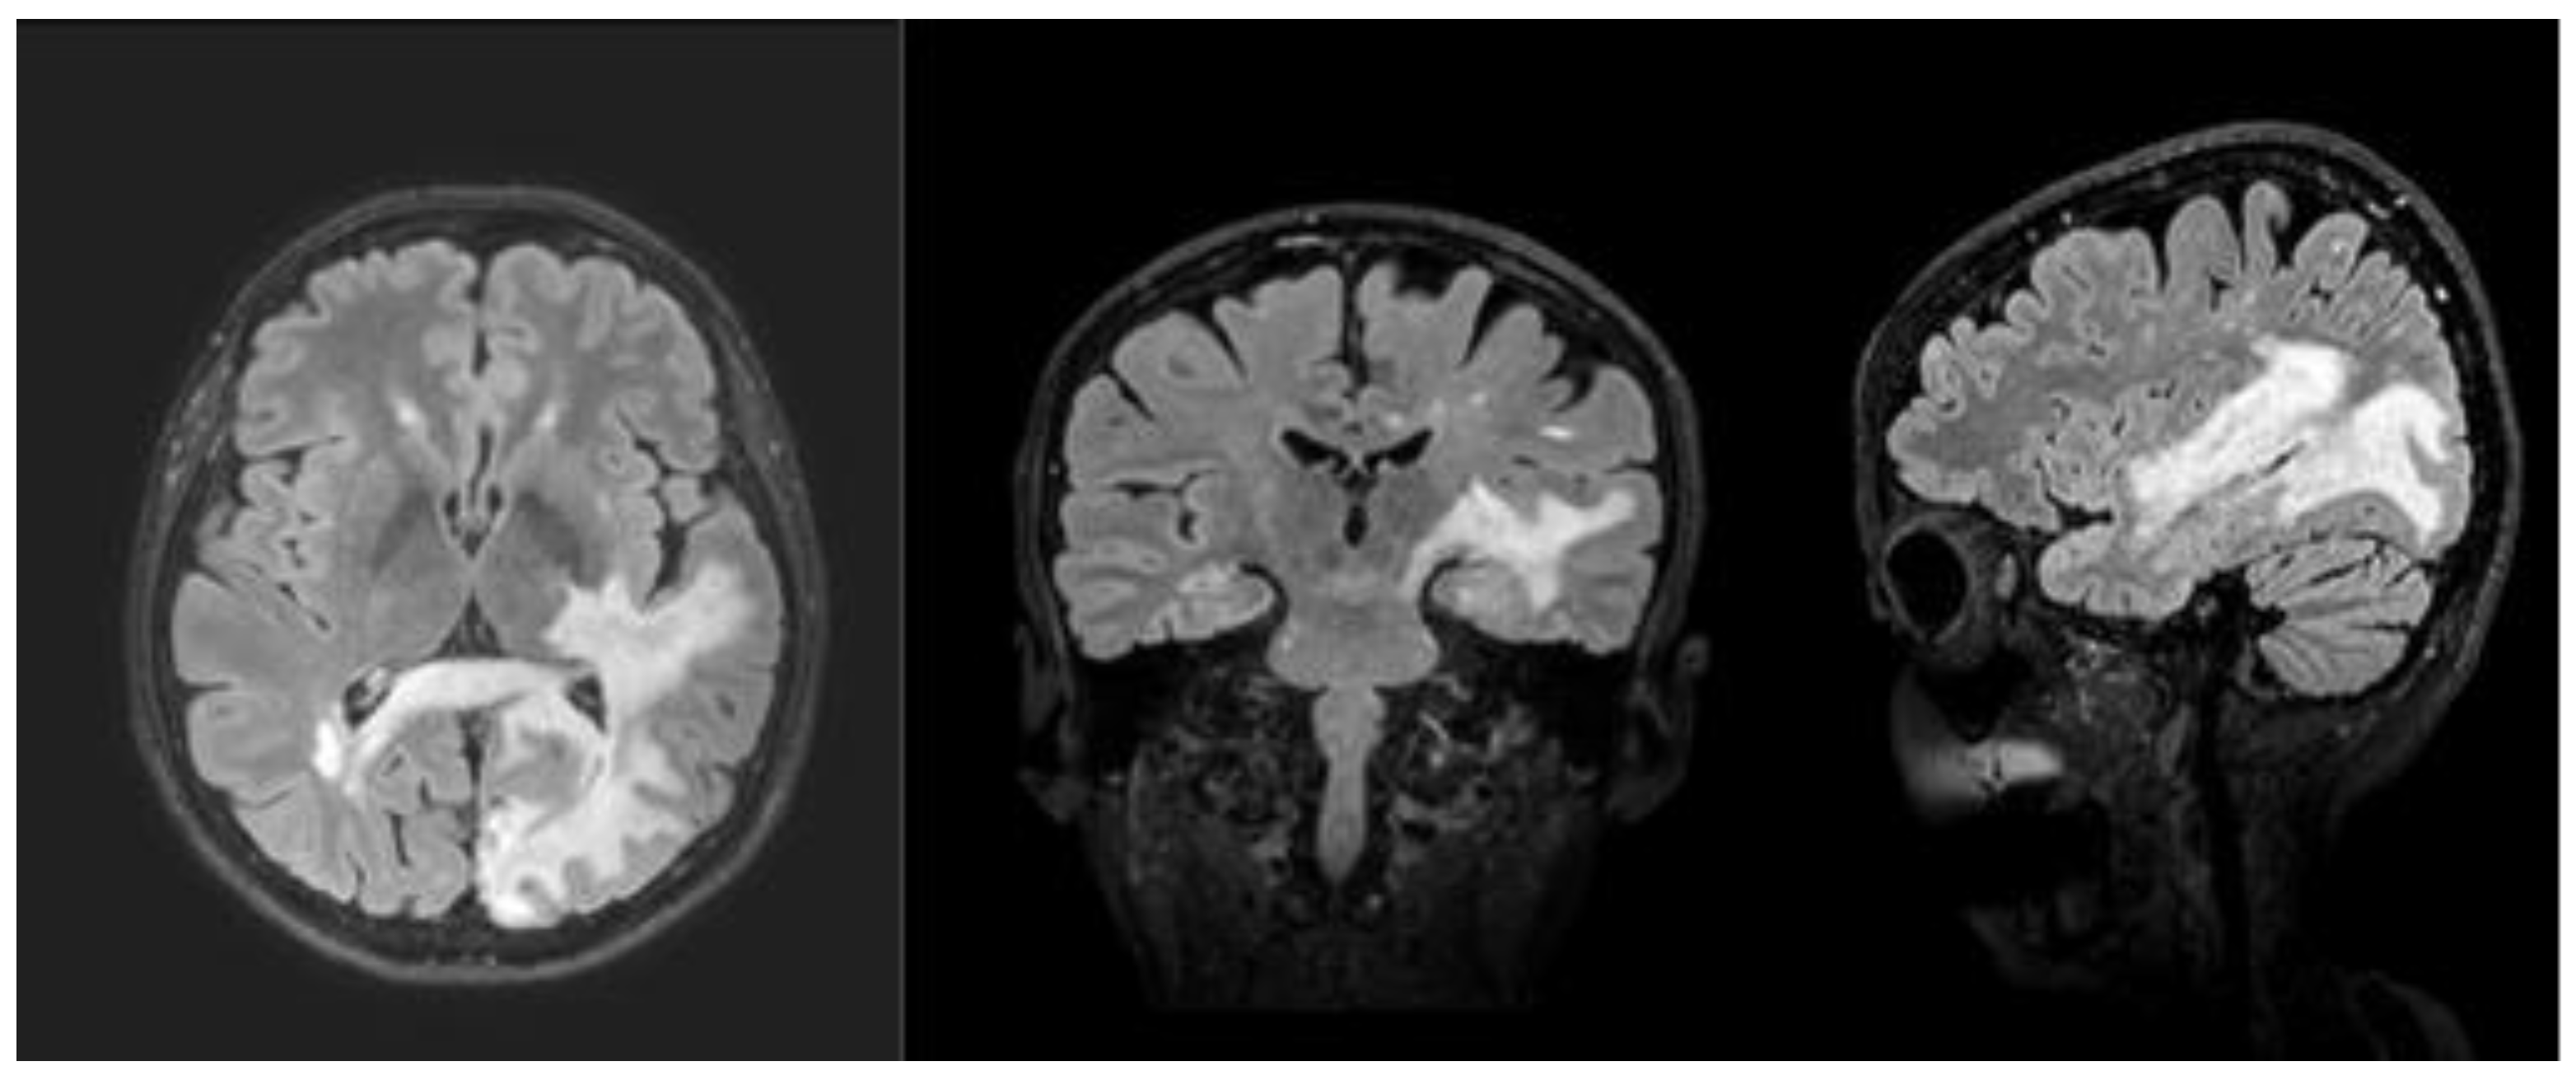

2. Case Presentation